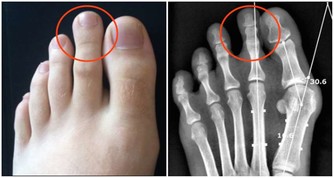

為什麼有些人洗牙之後會感覺牙齒變鬆了呢?

洗牙之後會覺得牙齒鬆了,這是因為牙周炎患者普遍存在嚴重的牙結石,

牙結石像水泥牆一樣粘在牙齒周圍,把所有牙齒全部捆在一起,讓你感覺牙齒看起來看很牢固,

所以當洗牙之後,把牙結石清掉,就會感覺牙縫大了,牙齒鬆了。

其實牙結石清掉,等待炎症消除後,這些情況都會改善的。

但是如果這些牙結石不能得到及時清理,久而久之,牙結石會一步步往齦下侵蝕,

最後導致牙槽骨萎縮,牙齦退縮,這也是引起牙齦萎縮的一大因素。